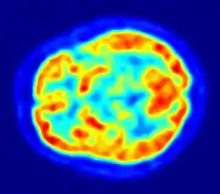

Although the human brain represents only 2% of the body weight, it receives 15% of the cardiac output, 20% of total body oxygen consumption, and 25% of total body glucose utilization.[137] The brain mostly uses glucose for energy, and deprivation of glucose, as can happen in hypoglycemia, can result in loss of consciousness.[138] The energy consumption of the brain does not vary greatly over time, but active regions of the cortex consume somewhat more energy than inactive regions, which forms the basis for the functional neuroimaging methods of PET and fMRI.[139] These techniques provide a three-dimensional image of metabolic activity.[140] A preliminary study showed that brain metabolic requirements in humans peak at about five years old.[141]

Functional neuroimaging techniques show changes in brain activity that relate to the function of specific brain areas. One technique is functional magnetic resonance imaging (fMRI) which has the advantages over earlier methods of SPECT and PET of not needing the use of radioactive materials and of offering a higher resolution.[155] Another technique is functional near-infrared spectroscopy. These methods rely on the haemodynamic response that shows changes in brain activity in relation to changes in blood flow, useful in mapping functions to brain areas.[156] Resting state fMRI looks at the interaction of brain regions whilst the brain is not performing a specific task.[157] This is also used to show the default mode network.